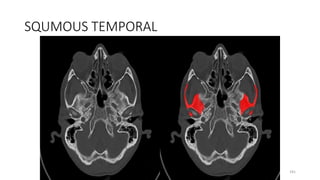

SQUMOUS TEMPORAL

181